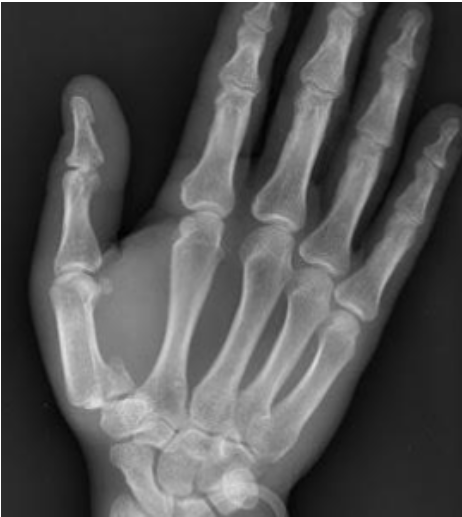

Que tipo de fractura es?

Fractura de Bennet

Mecanismo de lesion de esta fractura

Fuerza longitudinal a lo largo del eje del primer MTC con el pulgar flexionado.

Tratamiento de esta fractura

Clavillos de Kirschner